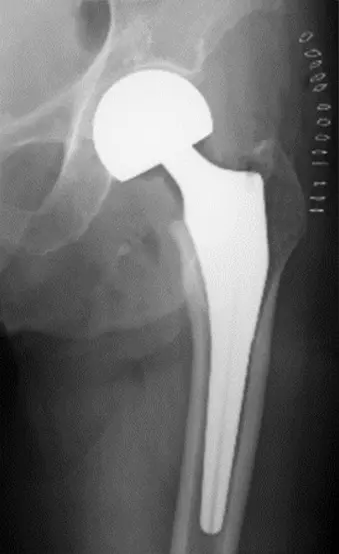

人工骨頭置換術における下双子筋近位の 外旋筋群温存後方アプローチについて

大腿骨頚部骨折に対する人工骨頭置換術後の骨頭脱臼は、一度脱臼すると再脱臼を繰り返し治療に難渋する。しかしながら大腿骨頚部骨折は高齢者での発生率が高いため、認知症を合併していることが多く、術後脱臼肢位の指導が困難であることが少なくない。今回、術後の後方脱臼リスクを軽減するため、下双子筋より近位の外旋筋群を温存する後方アプローチと外閉鎖筋・関節包の修復を行う術式を経験したので報告する。

画像所見

単純X線検査にて右大腿骨頸部骨折の所見(AO分類 31B)を認めた。

側臥位にて骨板固定器にて体位を固定し、股関節後方アプローチを施行。大腿方形筋近位を1/3~1/2程度切離し、下双子筋と大腿方形筋間を確認したうえ、下双子筋より近位の外旋筋群(下双子筋、内閉鎖筋、上双子筋および梨状筋)を近位へレトラクトする。外閉鎖筋を切離し、下双子筋よりやや近位で下双子筋と平行に関節包、坐骨大腿靭帯を切開する。関節包、坐骨大腿靭帯を切開した後に骨頭を抜去し、骨幹部を小転子より1横指近位で骨切りし髄腔をラスピングしたうえで、人工骨頭トライアルならびにインプラント(Cup 44mm, Stem size6, Neck +3mm)を挿入。試験整復を行い、屈曲60度・内旋90度で脱臼せず、90度 内旋90度で脱臼しない事を確認。創内を十分に洗浄後、外閉鎖筋腱と関節包をファイバーワイヤーにて大腿骨に強固に縫合し、閉創。

術後2日目より車椅子移乗訓練を開始。右下肢は僅かに拳上可能でステップには至らず解除要す状態であったが、術後4日目からはステップ可能、平行棒内歩行訓練も疼痛自制内で可能。術後4か月の現在、全荷重歩行中で脱臼も認めていない。